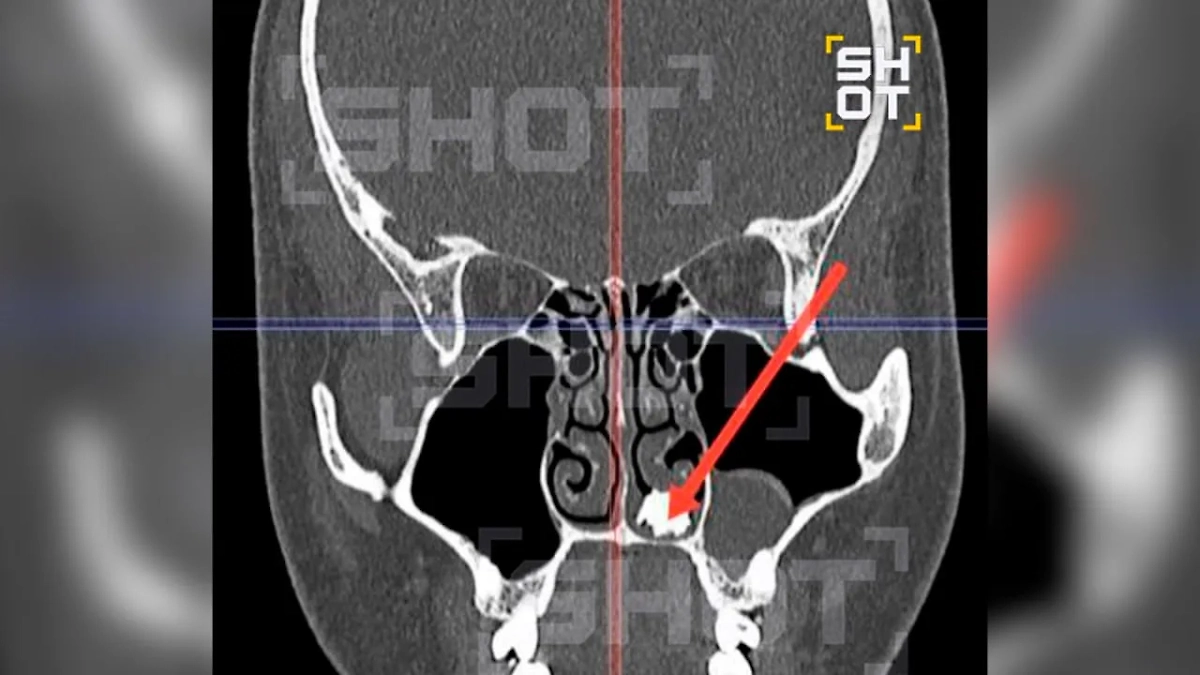

Зуб в носу 22-летнего жителя Подмосковья. Фото © SHOT

Коллеги из SHOT выяснили, что 22-летний молодой человек обратился в долгопрудненскую больницу с жалобами на насморк, который подозрительно долго не проходил. Медики провели пациенту диагностику и обнаружили у него в носу молочный зуб. Как он оказался не на своём месте, местный житель объяснить не смог.